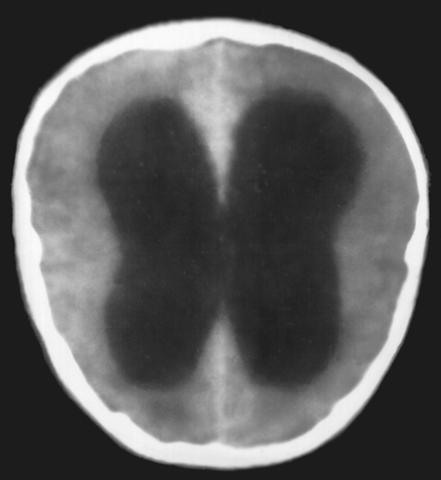

Рис. 2а). Компьютерная томограмма головы при окклюзии на уровне водопровода мозга воспалительного генеза.

Перейти к статье «

Окклюзионный синдром

»